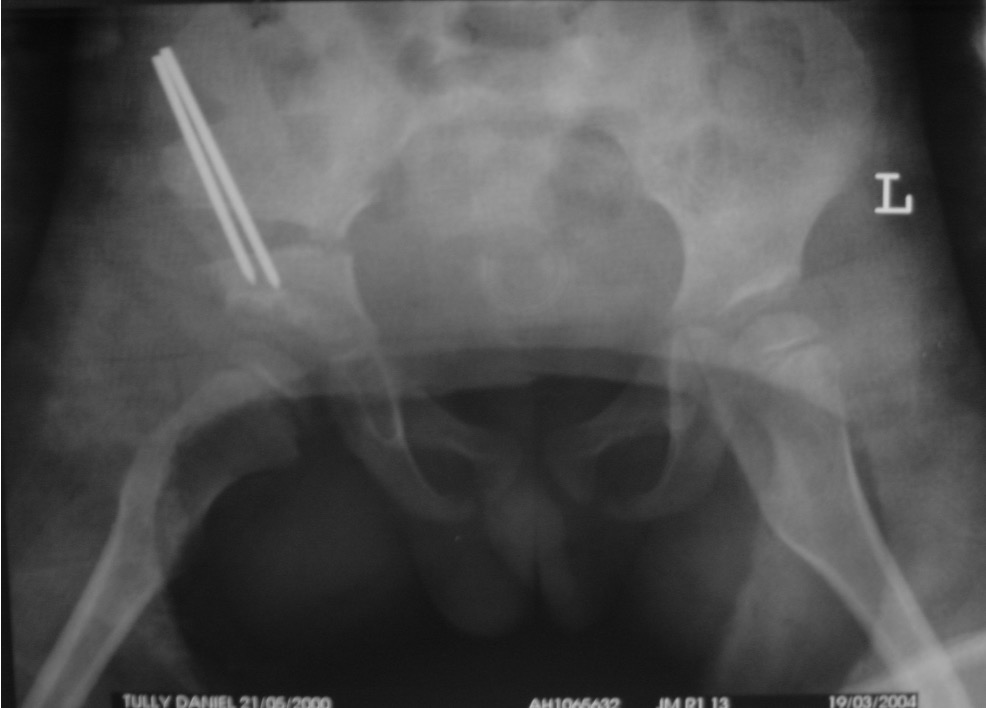

Osteotomy

- through greater sciatic notch to between ASIS and AIIS

- Gigli saw passed around greater sciatic notch

- osteotomy posterior to anterior

- acetabulum rotated anteriorly and laterally

- 15 mm triangular graft from iliac crest apophysis

- secure with K wire fixation

Salter complete osteotomy